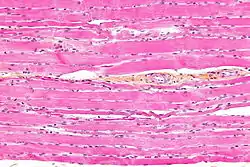

Striated muscle tissue is a muscle tissue that features repeating functional units called sarcomeres. The presence of sarcomeres manifests as a series of bands visible along the muscle fibers, which is responsible for the striated appearance observed in microscopic images of this tissue. There are two types of striated muscle:

Unlike skeletal and cardiac muscle tissue, smooth muscle tissue is not striated since there are no sarcomeres present. Skeletal muscles are attached to some component of the skeleton, and smooth muscle is found in hollow structures such as the walls of intestines or blood vessels. The fibres of striated muscle have a cylindrical shape with blunt ends, whereas those in smooth muscle are spindle-like with tapered ends. Striated muscle tissue has more mitochondria than smooth muscle. Both smooth muscle cells and cardiac muscle cells have a single nucleus, and skeletal muscle cells have many nuclei.[6]